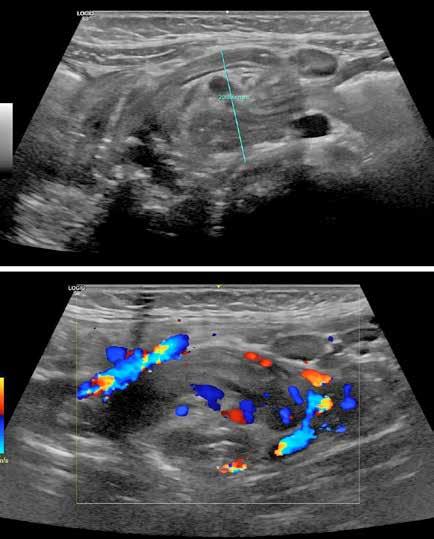

Debido al empeoramiento clínico se solicitó una ecografía de abdomen durante la cual estuvo presente el equipo tratante y en la que se evidenció aumento del líquido libre de aspecto ecogénico sin otras alteraciones. Sin embargo, ante la evolución tórpida y la localización de la contusión abdo minal se comunicó al radiólogo la posibilidad de una perforación intestinal, quien realizó una segunda exploración ecográfica enfocada en las zonas cefálicas y anteriores del abdomen en las que se ubicaría el aire, entonces se visualizaron artefactos en la superficie hepática que sugerían burbujas aéreasextraluminales (Figura 2A). Se realizó una radiografía toracoabdomi nal (RxTA) que confirmó la presencia de neumoperitoneo subdiafragmático bilateral (Figura 2B).

Figura 2. Ecografía con burbujas aéreas extraluminales en la superficie hepática sugestivas de neumoperitoneo (A, flechas). RxTA con neumoperitoneo subdiafragmático bilateral (B, flechas).